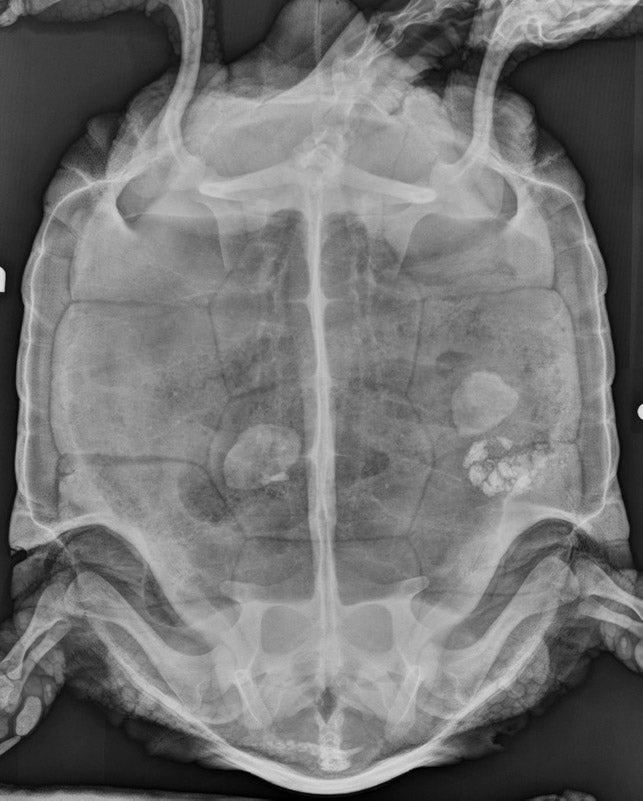

61-year-old tortoise treated for bladder stones

Mohave, a 61-year-old desert tortoise, was recently brought to the UC Davis veterinary hospital for a recurrence of bladder stones — an issue he was previously treated for in 2014. A few weeks ago, his caretakers noticed that his urates (a component of a reptile’s urine) were thick and pasty. Shortly thereafter, Mohave prolapsed his cloaca (a common exit for the urinary and gastrointestinal tract), most likely due to straining to eliminate the pasty urates.

“We took some radiographs and saw some distinct white shapes within his coelomic (abdominal) cavity,” said Juliana Sorem, head veterinarian at Wildcare, a wildlife hospital and nature education center in San Rafael, and Mohave’s home since 2003. “We compared the images with the radiographs taken at his last routine physical and didn’t see these objects on them. Given his clinical signs and the radiographic images, I was fairly certain the stones had recurred.”